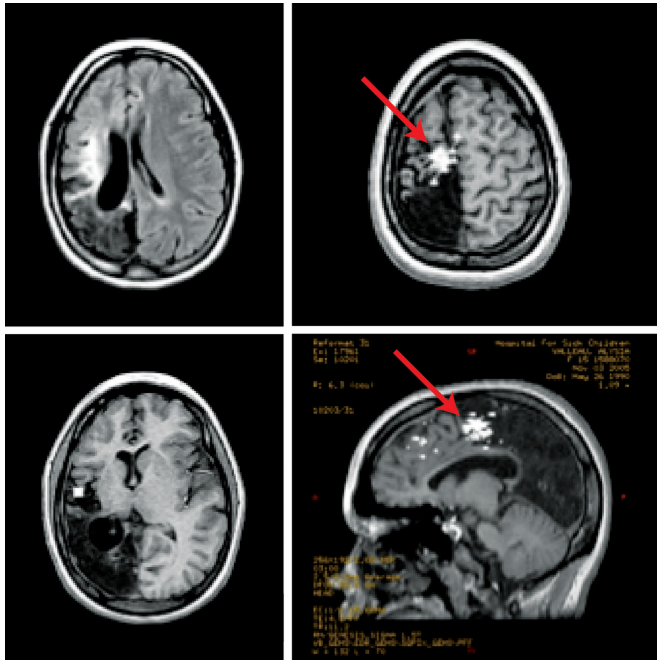

这是一名患有顽固性癫痫的12岁女孩。她曾在婴幼儿期遭受过创伤性脑损伤,导致右侧顶枕叶明显软化。MR显示左侧大脑广泛的软化灶,外伤性脑软化灶和正常Rolandic区皮质交界处有一个“spike cluster穗簇样”病灶(红色箭头),在进行了了影像引导下的MEG病灶切除术后,她恢复良好,目前已无癫痫发作。